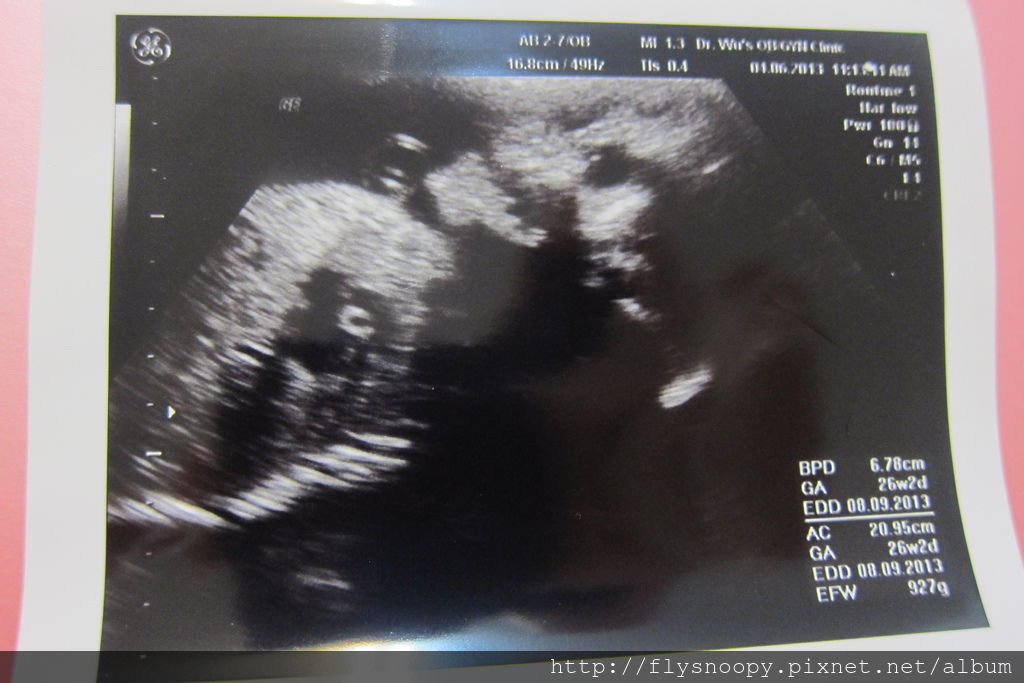

抽完血就照音波,但是這次的照片都滿不清楚的

EFW:927g

這次樂樂胎位轉正了,但是有臍帶繞頸的現象